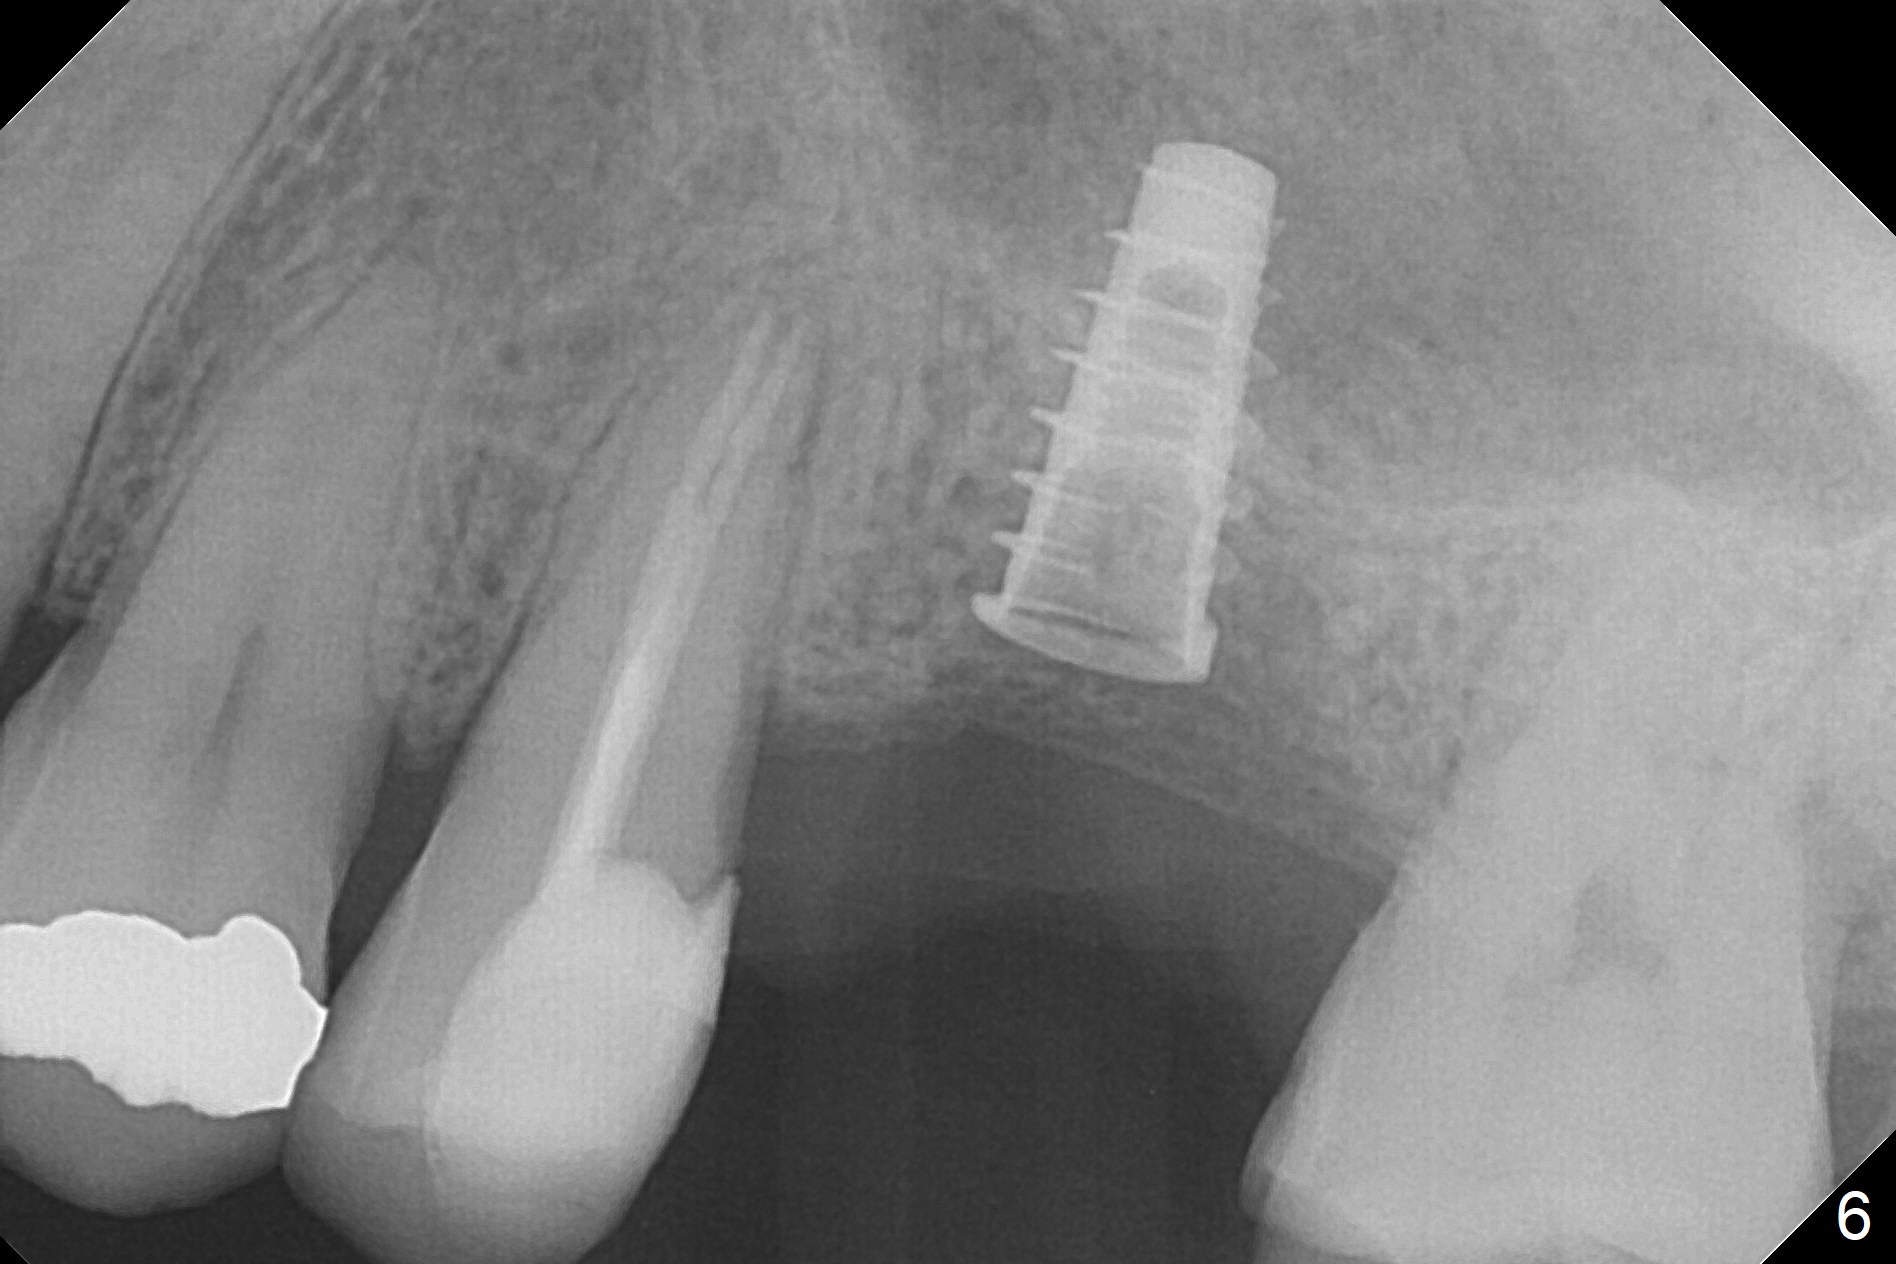

After extraction of the distobuccal residual root of the tooth #14 (Fig.1 arrow), the gingiva around the socket does not look like the keratinized one (Fig.2 *). An osteotomy through the distobuccal socket would seem too buccal for immediate implant. The palatal gingiva feels too tough to be stretched. An incision is made (Fig.3 dashed line); with elevation, the thick flap is transferred buccally (curved arrow). An osteotomy is initiated in the palatal bone with 1.5 mm drill, followed by Magic Expanders until 4.3 mm for 11 mm (Fig.4,5). Following Magic Drill 3.8x13 mm, the sinus membrane is found to be perforated. The latter is repaired with Osteogen plug. A 4.5x9 mm IBS implant is placed with 50 Ncm (Fig.6). Osteogen plug and allograft (Fig.7 *) are inserted into the remaining distobuccal socket (reduced after bone expansion). When a 5.5x4(4) mm abutment is placed, the transferred flap appears to be adapted to the distobuccal defect (Fig.8 *). Later one suture is placed for fixation. After provisional insertion, periodontal dressing is applied. Nine days postop, the periodontal dressing dislodges. When the loose provisional is removed for recementation, the flap seem to have healed (Fig.9 *). The gingiva heals around the abutment 5 months postop (Fig.9); the distal socket appears to heal while the bone graft remains at the crest (Fig.11,12). When #30 develops buccal abscess, the patient masticates on the left, leading to loss of composite at #13 (Fig.14); in fact the abutment at #14 is incompletely seated.